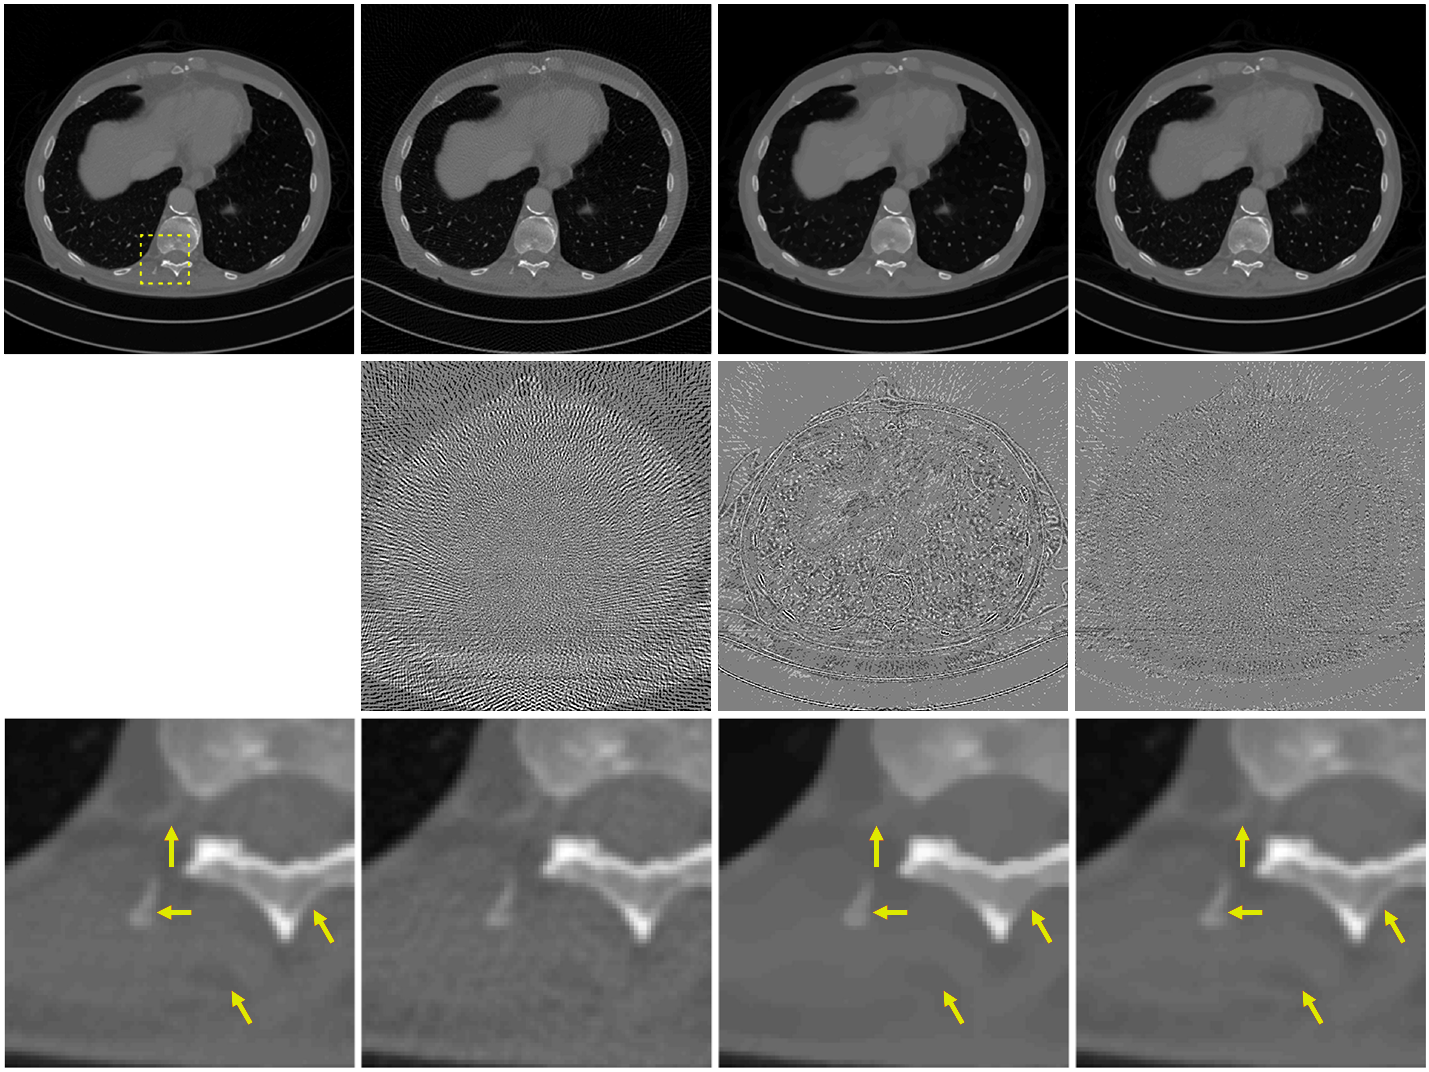

(a) Ground Truth | (b) SNR = 24.06 dB | (c) SNR = 29.06 dB | (d) SNR = 35.38 dB |

Most biomedical imaging modalities have a strong computational component, as they systematically rely on signal processing to reconstruct the images from the raw imaging data. The data can take the form of: (i) 2D projections of a 3D object as in X-ray tomography, PET, and cryo-electron microscopy, (ii) a series of blurred 2D slices of a specimen as in fluorescence microscopy, or (iii) samples of the Fourier transform of an object, as in MRI and optical diffraction tomography. By capitalizing on the knowledge of the imaging physics (linear forward model), the reconstruction task can then be formulated as an inverse problem. Until recently, classical imaging (MRI, CT) relied on a direct inversion of this forward model. This is achieved, for instance, by inverse Fourier transformation in MRI (with uniform sampling in k-space) or by inverse Radon transformation (the celebrated filtered-back-projection algorithm) in CT. This works well when the measurements are sufficiently numerous and diverse, and when the noise is negligible. Besides streamlining of the reconstruction process itself (improved non-uniform (NU) fast Fourier transform (FFT), optimization of sampling parameters, etc.), the earlier involvement of the SP community was to combat the effect of noise with the help of advanced statistical methods. One notable example of such success is the method of ordered subsets in PET and SPECT [15]. Another fruitful approach inspired by Wiener filtering is to inject prior information in a stochastic model (e.g., generalized Gaussian in a transformed domain), which makes a direct link between maximum a posteriori (MAP) reconstruction and regularization/energy minimization techniques [16]. The more significant revolution in imaging came with compressed sensing (CS) with theorists [17, 18] and then experimentalists [19, 20] showing the feasibility of image reconstruction from a reduced set of measurements. A milestone in this line of research was the development of efficient minimization methods under sparsity constraints, in particular the (fast) iterative soft thresholding algorithm (ISTA) and alternating direction method of multipliers (ADMM) [21]. The main benefit of CS is to enable faster imaging, which reduces not only cost but also radiation exposure (in the case of X-ray or PET/SPECT). This has led to a major revolution in MRI, with fast (CS-based) imaging protocols now offered by most vendors of MRI technology. While CS kept SPS researchers busy from 2005-2017, another wave then overtook the field—the incorporation of neural networks in the image reconstruction pipeline. This led to further significant improvement in image quality (Figure 5), especially in extreme scenarios, e.g., low signal-to-noise ratio and CS [14]. While image reconstruction based on convolutional neural networks (CNNs) still has shortcomings—they are poorly understood and can behave erratically (lack of stability, hallucination)—they demonstrate the potential of better reconstruction quality [22]. It is noteworthy that it took SP pioneers less than a year to tune their new CNN-based methods to the point where they would outperform sparsity-based methods for CS in public imaging challenges by the same margin (typically dB) than the latter had achieved over classical reconstruction during a whole decade of intense research activity. CNNs and learning-based techniques are presently at the center of attention of the researcher community. Recent trends include the development of more sophisticated iterative reconstruction schemes that rely on CNNs to regularize the solution—as enabled by the Plug-and-play framework [23]—as well as the use of deep learning for the resolution of more challenging non-linear inverse problems such as diffuse optical tomography (DOT) [24] and diffraction tomography.